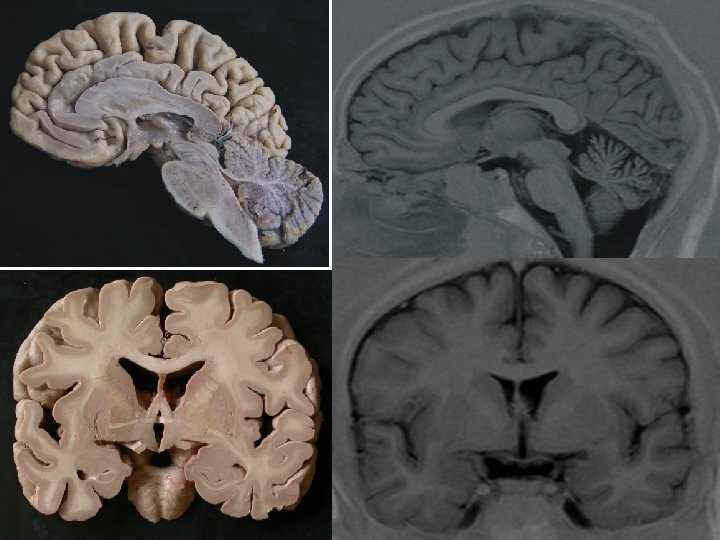

Obecné přístupy do dutiny lební • • • Vlasy Kůže Podkoží Kost Mozkové pleny

Podkoží a kost

Kost a dura mater